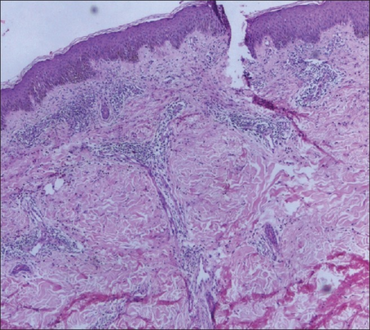

(Recurrent Cutaneous) Eosinophilic Vasculitis-perivascular inflammatory infiltrate in recurrent cutaneous eosinophilic vasculitis

Eosinophilic vasculitis is a cutaneous condition characterized by an inflammation of blood vessels and the presence of eosinophils.[1]